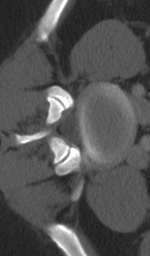

When an entire 3D volume needs to be super-resolved, all competing 3D CNN models need to use some form of patch-based algorithm that divides CT volumes into individual cubes to be inferred independently. However, such an approach introduces artifacts at the fringe, where the divided cubes are put back together. This is due to SISR models heavily employing padding555zero-padding is used for all models in this paper to keep the same dimensionality throughout convolutions, i.e. for every convolutional layer with a filter size of k𝑘k, the input tensor needs to be padded by k2𝑘2\lfloor\frac{k}{2}\rfloor for the output tensor to retain the same shape. For our implementation of the 3D RDN, there are fifty-two convolutional layers, which means the original input is padded by fifty-two voxels on each side, resulting in an overall padding size of 104×104×104104104104104\times 104\times 104. Such a large padding size distorts the real data distribution, and adversely affects voxel prediction accuracy, especially at the fringe, of the divided cues. As a result, when the cubes are reassembled together to form the super-resolved volume, the boundaries between them are often inconsistent. We refer to the artifact caused by this inconsistency as the stitching artifact.

The patch-based algorithm discussed in [4] attempts to alleviate this problem by introducing overlaps of three voxels between the divided 3D cubes, effectively replacing the padding of three initial convolution layers with real voxel values. As we have shown in Fig. 7 and an enlarged version in Fig. 8, this still leads to noticeable stitching artifacts with a deep network. Theoretically, to completely eliminate such artifact for 3D RDN, the input tensor needs to be padded with at least fifty-two voxels on each side, which leads back to memory bottleneck and inefficiency. In comparison, since SAINT breaks down 3D SISR into separate stages of 2D SISR, it completely eliminates stitching artifacts, thus also allowing for larger network size to be used.

Refer to caption

Figure 8: The stitching artifacts, following the procedure described in [4] with three voxel margin.